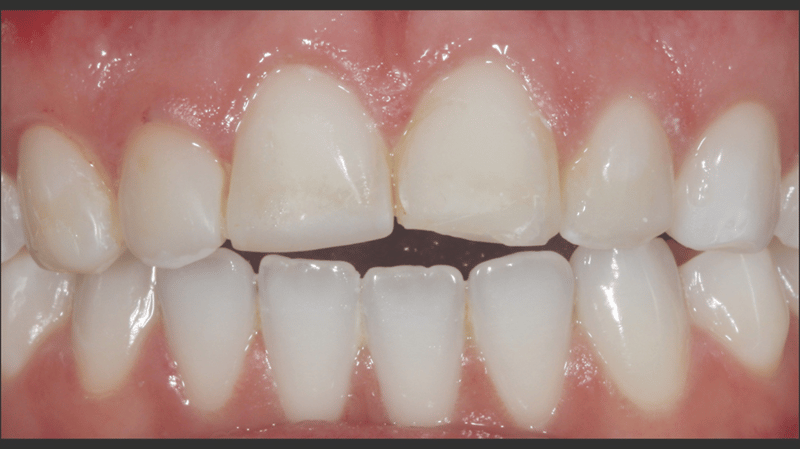

Een jonge vrouw van in de 20, die leed onder de verkleuring van haar bovengebit als gevolg van vroeger trauma, bezocht dr. Jaleena Fischer-Jessop omdat ze weer een mooie glimlach wilde. De patiënte kreeg een conserverende, betaalbare behandeling: directe adhesieve composietveneers zonder preparatie. Dr. Fischer-Jessop koos voor deze methode om de verkleuring te maskeren en de lengte van de bovenelementen aan te passen aan de frontelementen van de onderkaak, waardoor invasievere methoden, zoals implantaten of dure, indirecte veneers, niet nodig waren. De kleuren B1D en Enamel White (EW) werden geselecteerd om het gebit lichter te maken en met de Universal Body-kleur (UB) van Transcend™-composiet werd ervoor gezorgd dat de randen een natuurlijke overgang hadden naar de cervicale gebieden.

- Anamnese: Een vrouwelijke patiënt van in de 20 met een voorgeschiedenis van trauma aan de frontelementen in de bovenkaak. Ondanks het trauma bleven de gebitselementen stabiel, dus implantaten waren niet nodig.

- Esthetische en financiële afwegingen: De patiënte was niet tevreden over het uiterlijk van haar gebit en had het financieel gezien niet breed. Daarom werd gekozen voor directe adhesieve composietveneers zonder preparatie.